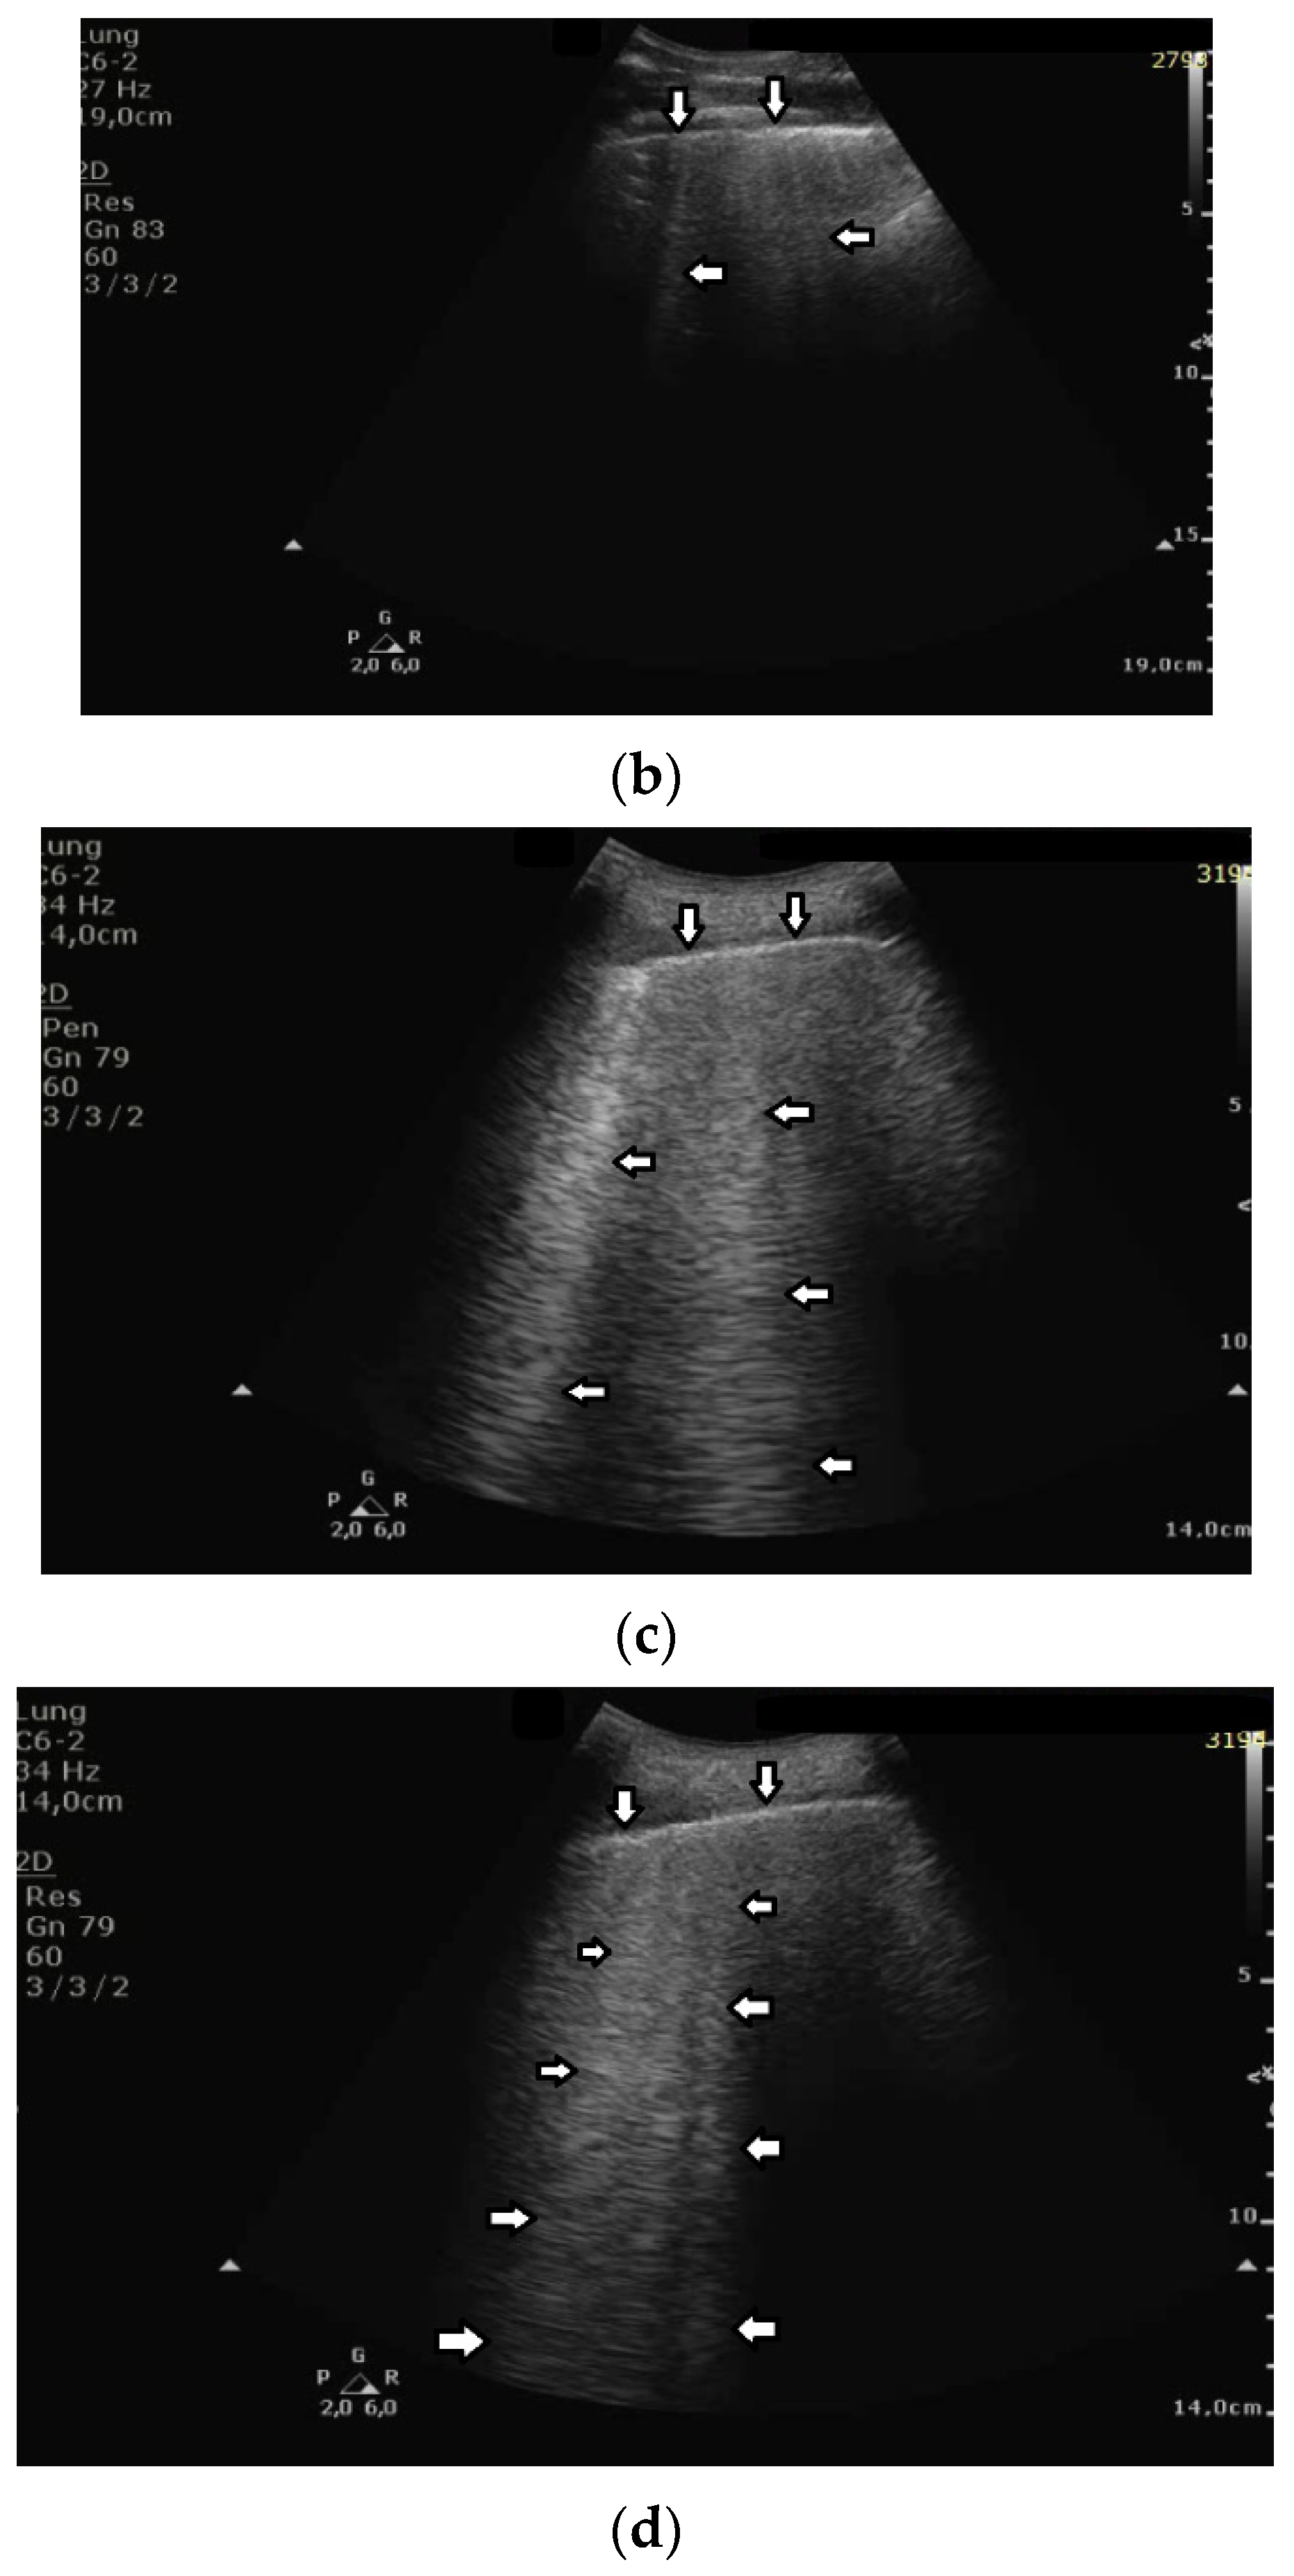

While monitoring the interstitial and alveolar involvement, we observe more and more confluent B lines which can evolve in a so-called white lung artifact which, in turn, can subsequently change to consolidation (see Figure 1) [5,6]. What does the image of B lines and consolidations depend on?

Isolated B lines are related to isolated acoustic traps and this probably occurs in the first stages of a pathology. When the number of the acoustic traps increases, due to the progression of a pathology, numerous B lines are observed. When their number further increases, they are close to each other and can be even mutually linked. In this case, confluent artifacts logically appear. When the ratio between aerated spaces and interstitial volumes drastically decreases within a lung region, then a lung configuration where small separated aerated spaces are immersed in an interstitial volume is expected. This is probably the lung configuration which is at the basis of the White Lung artifact. Obviously, when the last small aerated spaces also disappear, a clear consolidation naturally emerges.

Figure 1. Gradual loss of lung aeration in ultrasound. (a) normally aerated lung, (b) single vertical artifacts, (c) multiple vertical artifacts, and (d) subpleural consolidation.